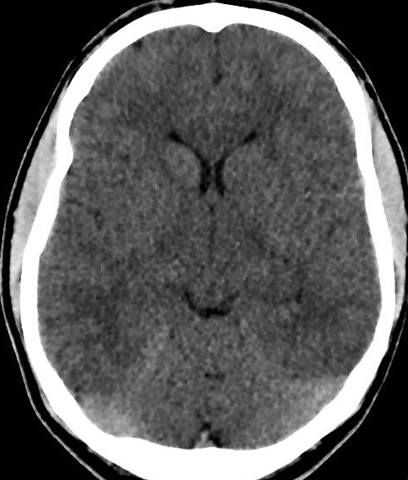

A 19-year-old male presented at the emergency department of the hospital on Saturday morning after a rave party. The patient arrived by ambulance after having had a seizure at the party. Other attendees of the party mentioned that the patient had consumed a large amount of water and (diluted) beer that night and had lost consciousness for a short time. On admission he was orientated with a maximum Glasgow Coma Scale (GCS) score of 15. He denied having used illicit drugs and his medical history was unremarkable. On physical examination the patient’s blood pressure was 147/117 mmHg and the heart rate regular at 114 beats per minute. His pupils were mildly dilated. The cardiovascular and respiratory examination were normal, no crackles were heard. The patient, however, appeared hypervolemic. His face had an edematous appearance and he visited the toilet several times while awaiting the results of the initial investigations. Shortly after being admitted, he experienced tonic-clonic seizure, for which midazolam was administered. To rule out intracranial pathology, a brain computed tomography (CT) scan was performed which showed evidence of cerebral swelling (Figure 1). Laboratory test findings on admission were as follows: sedimentation rate in the first hour: 2 (normal range <15), serum hemoglobin 8.6 mmol/l (normal range 8.5–11.0), leucocytes 13.0x109/l (normal range 4–10), sodium 119 mmol/l (normal range 135–145), creatinine 71 umol/l (normal range 65–110), osmolality 265 mOsmol/kg (normal range 275–300) and CK 1147 U/l (normal range <200). The serum ethanol level was 0.4 (normal range < 0.50/00), while the urine osmolality was 460 mOsmol/kg and the urine sodium level was 113 mmol/l. Urine toxicology screens for XTC and methamphetamine were positive. A diagnosis of acute, symptomatic hyponatremia associated with XTC intoxication was made. The patient was initially treated with hypertonic saline (50 ml of 3% NaCl per hour). The neurologist started the patient on intravenous Depakine to prevent new seizures. Several hours after admission, the patient’s sodium level remained stable at 120 mmol/l. Meanwhile the patient experienced two additional seizures. Due to the patient’s refractory clinical condition, we decided to treat him with a low dose loop diuretic, so 10 mg of furosemide was administered intravenously. A diuresis of 6900 ml in six hours then followed and the hyponatremia was gradually corrected, reaching 137 mmol/l the next morning (24 hours after admission). The patient was discharged from the hospital the following day, without any sequelae.

Figure 1: Computed tomography scan of the brain demonstrating diffuse swelling and edema.